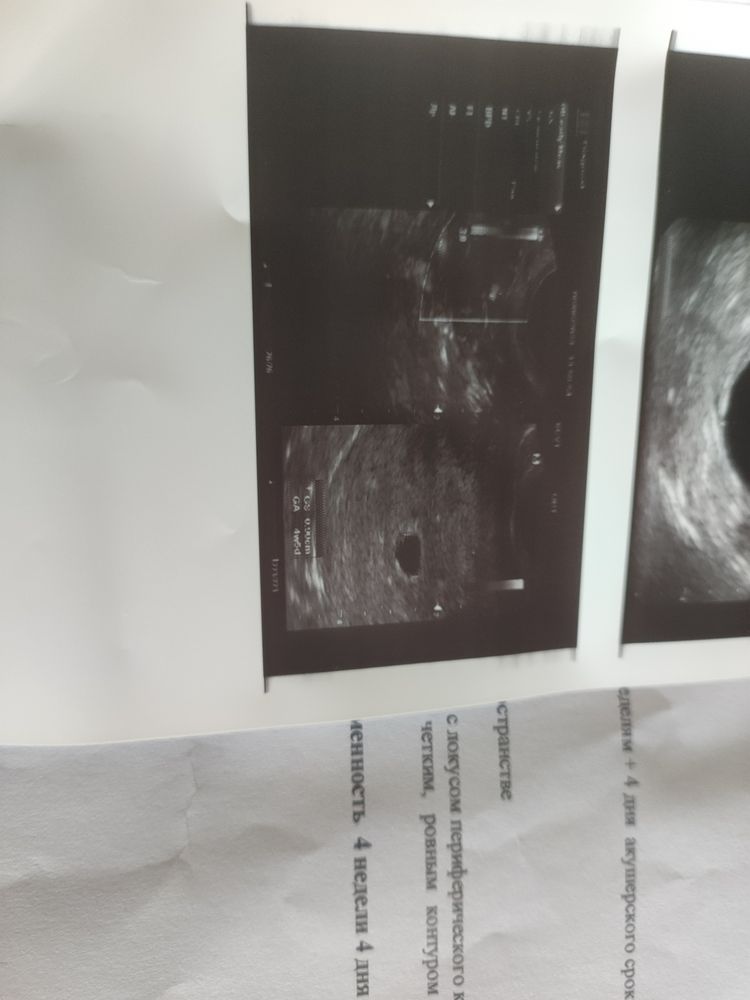

Сходила сегодня на УЗИ. Поставили 4 недели и 4 дня. Всё по сроку. Но нашли какое-то объемно жидкостное образование у правого яичника. Кто с таким сталкивался? Врач говорит если меньше не станет операция лапароскопическая делается.

По описанию - Фолликулярная киста с прошлого цикла, скорее всего.

Наблюдать в динамике.